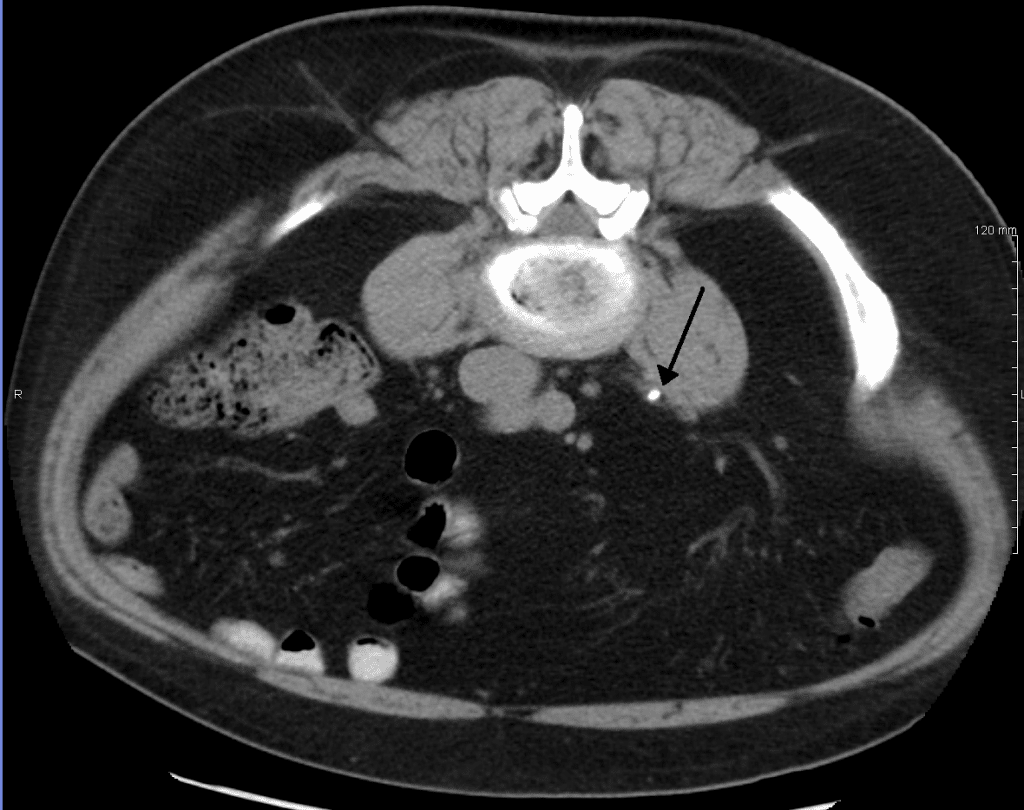

The ureters are two thick tubes which act to transport urine from the kidney to the bladder. They are approximately 25cm long and are situated bilaterally, with each ureter draining one kidney. In this article, we shall look at the anatomy of the ureters – their anatomical course, neurovascular supply and clinical correlations. Pro Feature - 3D Model You've Discovered a Pro Feature Access our 3D Model Library Explore, cut, dissect, annotate and manipulate our 3D models to visualise anatomy in a dynamic, interactive way. Learn More Anatomical Course The ureters arise in the abdomen as a continuation of the renal pelvis, and terminate in the pelvic cavity – where they empty into the bladder. The anatomical course of the ureters can therefore be divided into abdominal and pelvic components. Abdominal Part The ureters arise from the renal pelvis – a funnel like structure located within the hilum of the kidney. The renal pelvis receives urine from the major calyces. The point at which the renal pelvis narrows to form the ureter is known as the ureteropelvic junction. After arising from the ureteropelvic junction, the ureters descend through the abdomen, along the anterior surface of the psoas major. Here, the ureters are a retroperitoneal structure (located behind the peritoneum). At the area of the sacroiliac joints, the ureters cross the pelvic brim, thus entering the pelvic cavity. At this point, they also cross the bifurcation of the common iliac arteries. By TeachMeSeries Ltd (2025) Fig 1The anatomical course of the ureters from the renal pelvis to the bladder. Pelvic Part Once within the pelvic cavity, the ureters travel down the lateral pelvic walls. At the level of the ischial spines, they turn anteromedially, moving in a transverse plane towards the bladder. Upon reaching the bladder wall, the ureters pierce its lateral aspect in an oblique manner. This creates a one way valve, where high intramural pressure collapses the ureters – preventing the back-flow of urine. Clinical Relevance Vascular Relations of the Ureters The anatomical course of the ureters is of surgical importance, as they travel close to other structures in the pelvis. They must be identified during pelvic surgery to ensure that they are not accidentally damaged. Female As they cross the pelvic brim, the ureters are in close proximity to the ovaries. Care must be taken not the damage the ureters during an oophorectomy, especially during the ligation of the ovarian arteries. Approximately 2cm superior to the ischial spine, the ureters run underneath the uterine artery. During a hysterectomy, where the uterus and uterine artery are removed, the ureter is in danger of being accidentally damaged. The relationship between the two can be remembered using the phrase ‘water under the bridge’. By TeachMeSeries Ltd (2025) Fig 2Relationship between the ureter and uterine artery. Male In men, instead of the uterine arteries, the vas deferens cross the ureters anteriorly. Neurovascular Supply The ureter is a structure that has developed via the ureteric bud from the mesonephric duct, and then followed the kidney during its ascend to the final lumbar position in the retroperitoneum. This long, ascending course has enabled the ureter to acquire vessels (arteries, veins and lymph vessels) of different origin during its route. The arterial supply to the ureters can be divided into abdominal and pelvic supply: Abdominal – renal artery, testicular/ovarian artery, and ureteral branches directly from the abdominal aorta Pelvic – superior and inferior vesical arteries. Venous drainage is carried out by vessels that correspond to the aforementioned arteries. Nervous supply to the ureters is delivered via the renal, testicular/ovarian and hypogastric plexuses. Sensory fibres from the ureters enter the spinal cord at T11-L2, with ureteric pain referred to those dermatomal areas. Despoina @ PatrasAnatomy Fig 3The neurovascular and lymphatic supply to the ureters. Clinical Relevance Ureteric Calculus A ureteric calculus (or kidney stone), is the presence of a solid stone in the urinary tract, formed from minerals within the urine. These can obstruct urinary flow, causing renal colic (an acute and severe loin pain) and haematuria (blood in the urine). There are three locations where the ureters are at their narrowest – this is where a stone is more likely to become stuck: Uretopelvic junction Pelvic brim Where the ureter enters the bladder The gold standard investigation for suspected ureteric calculus is CT scan of the kidneys, ureters and bladder (CT-KUB). By James Heilman, MD [CC BY-SA 3.0] Fig 4A ureteric stone on CT KUB Do you think you’re ready? Take the quiz below Pro Feature - Quiz The Ureters Question 1 of 2 Submitting... Skip Next Rate question: You scored 0% Skipped: 0/2 1800 More Questions Available Upgrade to TeachMeAnatomy Pro Challenge yourself with over 1800 multiple-choice questions to reinforce learning Learn More Rate This Article